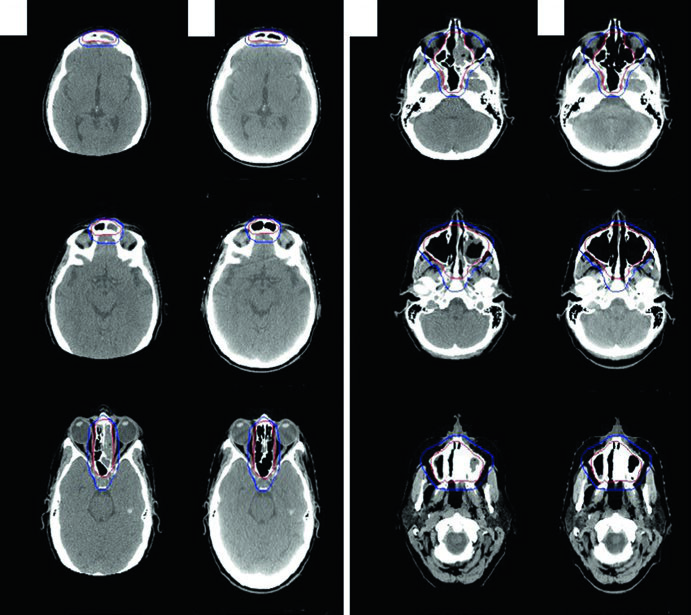

CT simulation axial slices showing orbital MALT lymphoma delineation with GTV in red, CTV covering the entire orbit in green, and PTV in blue

Figure 31.7 — Orbital MALT lymphoma: GTV (red), CTV covering the whole orbit (green), and PTV (blue). Source: Target Volume Delineation and Field Setup, 2nd Edition

Patients are simulated supine, arms down, head immobilized with a thermoplastic mask. For orbital lymphoma, technique options include a superior-inferior wedge pair, 3DCRT, or IMRT. Bolus may boost superficial dose in localized soft tissue disease. Consider lacrimal gland shielding if the prescribed dose reaches 30 Gy or above.

For limited indolent conjunctival disease, anterior electron beam setup or mixed electron/photon energy is an alternative; consider lens shielding if the tumor is peripheral. Sinonasal lymphomas warrant 3DCRT or IMRT given the higher doses required and the number of surrounding critical structures.